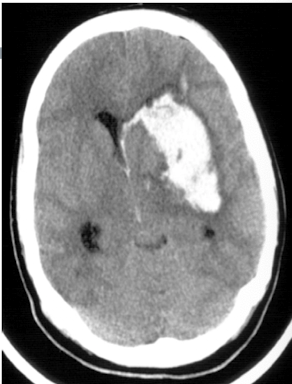

8

Q

where is the blood

A

subdural

How well did you know this?